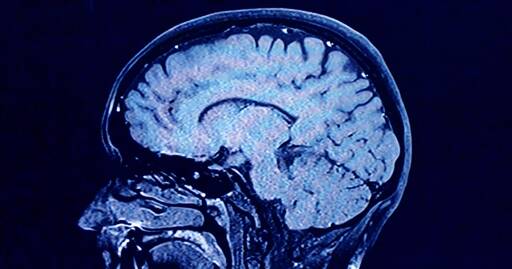

Human brains have 5 distinct 'epochs' in a lifetime, study finds

During each of these phases, our brains show markedly different characteristics in their architecture, according to the new findings.